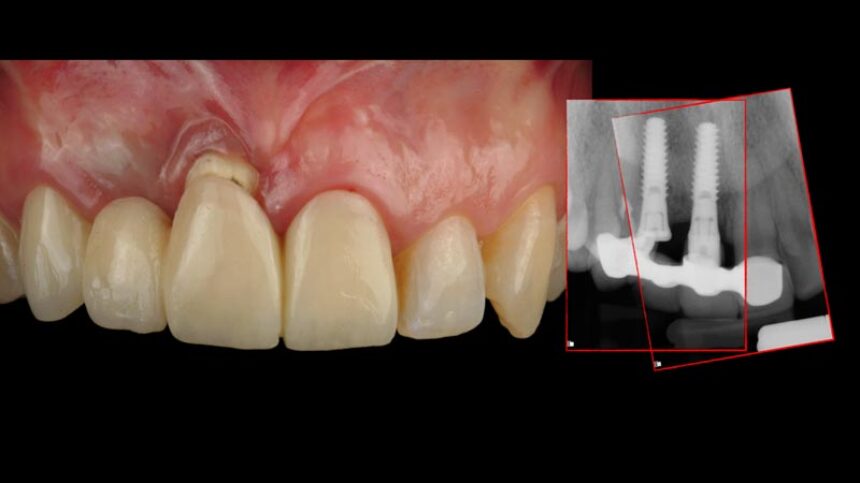

Managing failures with implants in the esthetic area, the options.

Understand the importance of CTG around dental implants for long term results

Diagnosis, prevention and treatment of peri-implantitis